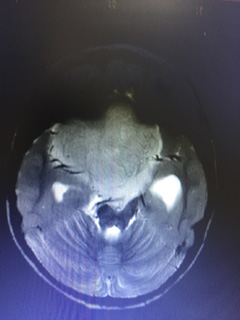

Pediatric Brain Tumors Surgery in Dehradun, Uttarakhand

Pediatric (Child) Brain Tumour Operated